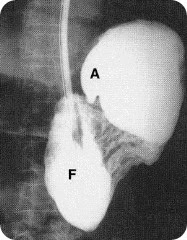

x ray of volvulus gastric

Gastric volvulus is a rare condition encountered in the adult as well as the pediatric age group. The majority of cases are of the mesenteroaxial type rather than the organoaxial type.Anomalies associated with acute gastric volvulus include diaphragmatic defects‚ intestinal malrotation‚ and wandering spleen. Most cases of gastric volvulus seem to be secondary to deficient fixation. Absence of the gastrophrenic ligament and the gastrosplenic ligament as well as an absence of the spleen may lead to gastric volvulus in asplenic patients. Elongation or absence of the splenorenal ligament even with preservation of the gastrosplenic ligament may lead to mesenteroaxial gastric volvulus